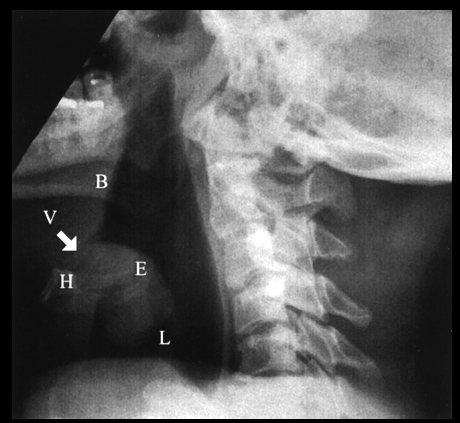

【正常な解剖がわかりやすいレントゲン写真】

nasopharynx:鼻咽頭

soft palate:軟口蓋

hypopharynx:下咽頭

epiglottis:喉頭蓋

trachea:気管